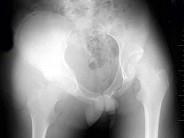

问题 男,18岁,右髋关节肿胀,疼痛1月余,经抗感染治疗,疗效不佳,结合图像,最可能的诊断是?(?)

选项 A.右髋关节软骨肉瘤 B.右髋关节滑膜肉瘤 C.右髋关节纤维肉瘤 D.右髋关节化脓性关节炎 E.以上均不是

答案 B